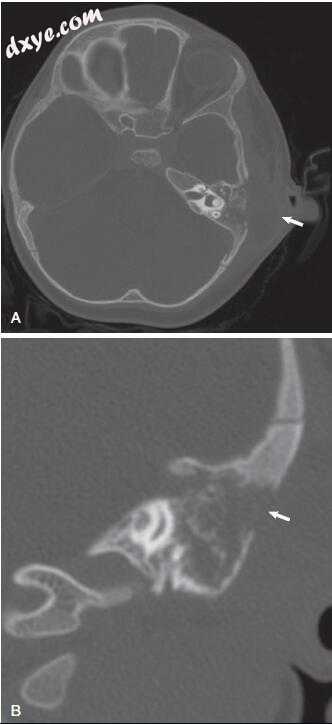

图-5. 轴向颞骨计算机断层扫描(软组织)显示伴有气体的脓肿腔(箭头)。 注意皮质缺损(箭头),乳突浑浊和骨质隔膜(星号)丢失。